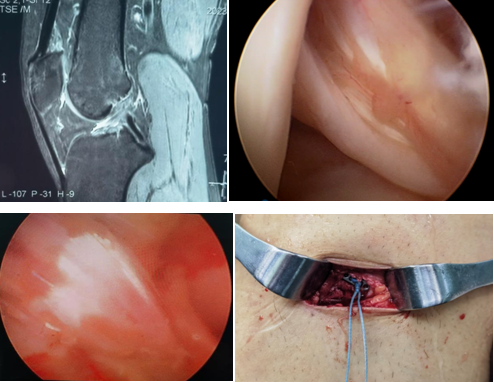

近日,一名31岁男性因打篮球扭伤致“右膝关节疼痛伴行走不稳半年”入院,术前诊断:前交叉韧带部分断裂。考虑患者年轻且有较高的运动恢复需求,在骨科病院刘时璋主任医师的指导下,由冯敏副主任医师主刀完成21点技巧中心

首例关节镜辅助下前交叉韧带损伤“保残+全内”重建术。患者第二日即下地活动,第三天顺利出院。

ACL的保残重建具有有效促进ACL移植物血管再生,促进损伤ACL本体感觉的恢复,以及防止ACL术后隧道扩大等多种技术优势。而ACL的全内重建技术是国际上新近发展出现的另一项新技术,相比传统方法,它仅需获取自身单根肌腱,而且所需长度远小于传统重建方法。另外,此技术保留了更多的骨皮质及骨膜,术后疼痛更少,腱骨愈合更佳,同时有效降低了术后感染风险,避免了传统方式界面螺钉对肌腱的切割作用。